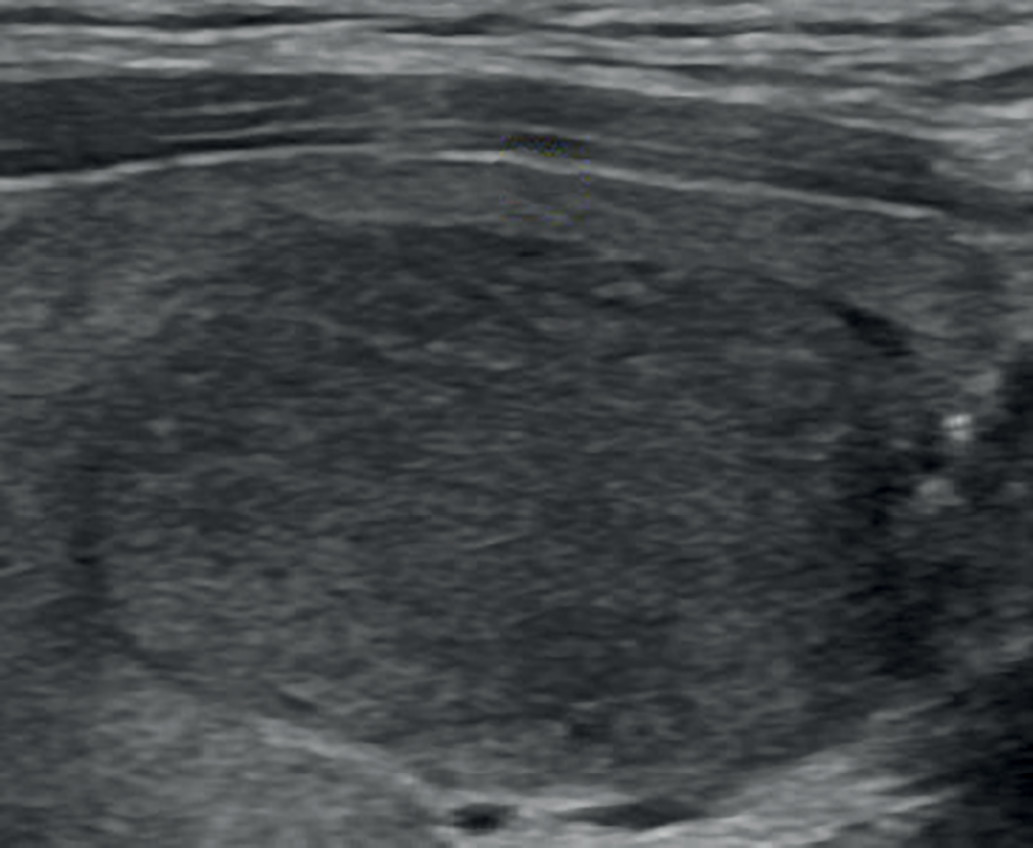

2. Рис. 2. Изоэхогенное образование ЩЖ с ровными контурами (EU-TIRADS 3). | |